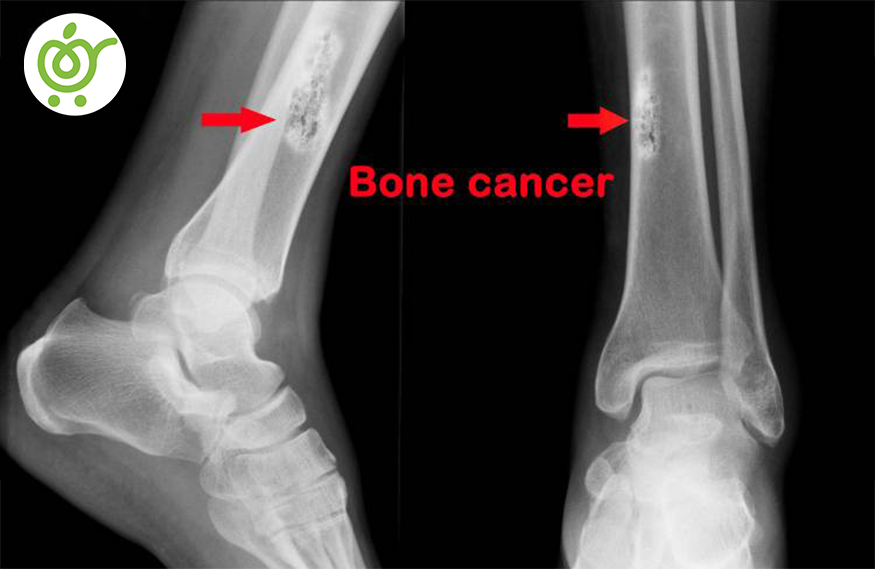

سرطان استخوان

اگر یک تومور یا تودهای به صورت کاملاً غیر طبیعی در استخوان، شروع به رشد کردن کند، به اصطلاح یه این نوع بیماری، سرطان استخوانی گویند. گرچه سرطانی که از استخوان شروع شود نادر است اما در اکثر مواقع، سرطان از اندام دیگر شروع شده و به استخوان منتقل میشود.